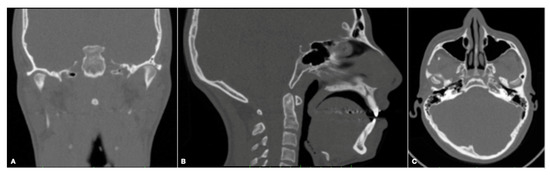

2. Materials and Methods